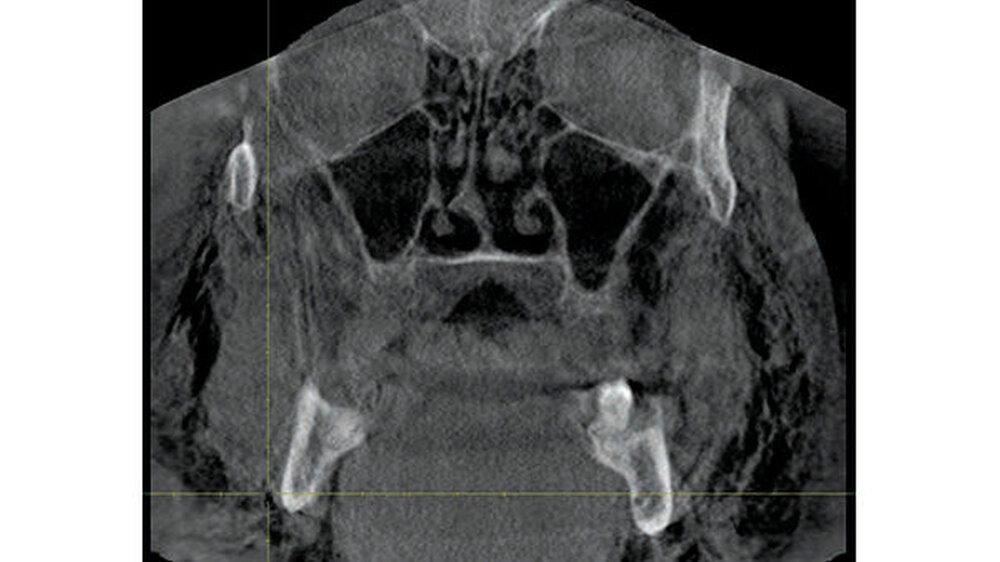

Zum Ausschluss einer Mittelgesichtsfraktur bei palpatorischem Weichteilemphysem erfolgte zur weiteren Diagnostik eine DVT-Aufnahme. Es zeigten sich keine Frakturen im Bereich des Mittelgesichts oder der Kiefer. Jedoch kam in der DVT-Bildgebung sowie der OPT-Optik ein massives Weichgewebeemphysem zur Darstellung (Abbildungen 2 bis 5).

Weiterhin wird deutlich, dass bei in aller Regel doch sehr eingeschränkter Beurteilbarkeit von Weichgewebe im DVT in diesem speziellen Fall eine weiterführende Diagnostik und Therapie eingeleitet werden konnte.

Das Emphysem war initial im DVT so eindrucksvoll sichtbar, dass es trotz fehlender klinischer Symptomatik im Thoraxbereich des Patienten, schwieriger Anamnese und blander zweidimensionaler Bildgebung der Lunge (RÖ-Thorax) der Faktor für eine weitere dreidimensionale Bildgebung (CT-Thorax) war, der letztendlich die Verdachtsdiagnose sicherte.

Zur Frakturdiagnostik im Mittelgesichtsbereich eignet sich das DVT sehr gut, außerdem ist die freie Luft des Emphysems im undifferenzierten Weichgewebe gut darstellbar.